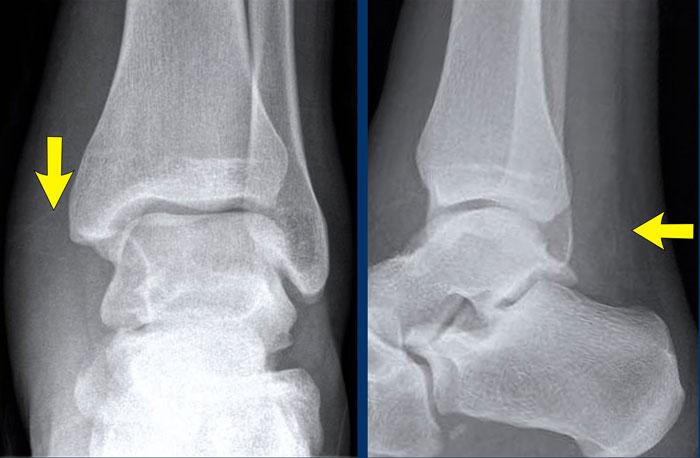

case 3 – distortion

Đây là một trường hợp khác của gãy xương mắt cá sau.

Again we have to look at the algoritm for ankle fractures…

Gãy mắt cá sau được thấy trong gãy xương Weber B hoặc Weber C.

Trong trường hợp này, chúng ta đã thấy một gãy xương chéo của mắt cá ngoài, điều này có nghĩa là chúng ta đang đối mặt với gãy xương Weber B.

Bây giờ chúng ta chỉ cần xác định đây là giai đoạn nào.

Giai đoạn 2 phổ biến nhất là ổn định, nhưng giai đoạn 3 và 4 thì không ổn định.

Trong trường hợp này, chúng ta đã ở giai đoạn 3 và muốn tìm kiếm các dấu hiệu của giai đoạn 4.

Một khối sưng mô mềm đau khi thăm khám đã có thể chỉ ra giai đoạn 4, nhưng trong trường hợp này còn có thêm.

Có thể bạn muốn quay lại xem phim X-quang trước khi tiếp tục đọc…

In this case we are looking for a stage 4.

Bây giờ bạn chú ý đến sưng phần mềm ở phía trong (mũi tên).

Tuy nhiên, phát hiện quan trọng nhất là sự không đều và tính thấu quang của phần trên mắt cá trong.

Nếu dùng trí tưởng tượng, bạn có thể xác định một đường gãy ở đây, điều mà bạn sẽ không nhận ra nếu không sử dụng thuật toán.